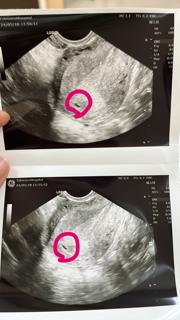

入籍して2ヶ月、旦那が交通事故で入院中に妊娠発覚。退院を待って病院に行くはずが、茶オリ?出血?と腹痛があって心配ですぐに病院へ。出血に関しては何も言われなかったから大丈夫なのかな?計算では5w1dだったけど4w0dと言われました(*´・ェ・`*)次は一緒に!2週間後がドキドキです。

さすがにまだ赤ちゃんは見ることはできませんでしたが、卵黄嚢は発見^o^ このまま順調にそだってくれ~!

妊娠検査薬して1週間後に病院に行きました?まだ何週かわからないです↓ 次はまた来週です。不安もたくさんだけど、楽しみー☆*:.。.o(≧▽≦)o.。.:*☆

2回目の妊娠。 またお腹の中にきてくれましたっ。 次はちゃんと育てたい~ まだまだ小さいけど頑張ります☆ 予定日1210~

出血があり心配で初めてお医者さんに行ったら、超音波で胎嚢発見。 出血が多くなったらすぐに来てと言われ今は少なくなってきてるので来週にまた検査! 胎嚢が大きくなってれば来週におめでとうと言ってもらえます♪ 不安ばかりだけど、旦那が俺らの子供なら強いでしょと言っていたので、赤ちゃんを信じて一緒に頑張っていきます(*・з・*) 大きくなっているように赤ちゃんの生命と神様にお願いだ!あとは私も頑張らなくちゃ!

胎嚢7.3mmでした。